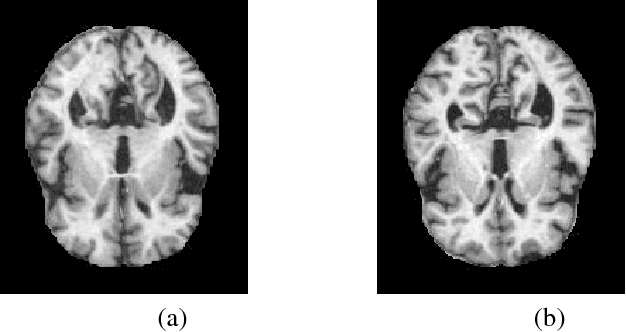

Abstract:Detection of Alzheimer's Disease (AD) from neuroimaging data such as MRI through machine learning has been a subject of intense research in recent years. Recent success of deep learning in computer vision has progressed such research further. However, common limitations with such algorithms are reliance on a large number of training images, and requirement of careful optimization of the architecture of deep networks. In this paper, we attempt solving these issues with transfer learning, where the state-of-the-art VGG architecture is initialized with pre-trained weights from large benchmark datasets consisting of natural images. The network is then fine-tuned with layer-wise tuning, where only a pre-defined group of layers are trained on MRI images. To shrink the training data size, we employ image entropy to select the most informative slices. Through experimentation on the ADNI dataset, we show that with training size of 10 to 20 times smaller than the other contemporary methods, we reach state-of-the-art performance in AD vs. NC, AD vs. MCI, and MCI vs. NC classification problems, with a 4% and a 7% increase in accuracy over the state-of-the-art for AD vs. MCI and MCI vs. NC, respectively. We also provide detailed analysis of the effect of the intelligent training data selection method, changing the training size, and changing the number of layers to be fine-tuned. Finally, we provide Class Activation Maps (CAM) that demonstrate how the proposed model focuses on discriminative image regions that are neuropathologically relevant, and can help the healthcare practitioner in interpreting the model's decision making process.

Abstract:Detection of Alzheimer's Disease (AD) from neuroimaging data such as MRI through machine learning have been a subject of intense research in recent years. Recent success of deep learning in computer vision have progressed such research further. However, common limitations with such algorithms are reliance on a large number of training images, and requirement of careful optimization of the architecture of deep networks. In this paper, we attempt solving these issues with transfer learning, where state-of-the-art architectures such as VGG and Inception are initialized with pre-trained weights from large benchmark datasets consisting of natural images, and the fully-connected layer is re-trained with only a small number of MRI images. We employ image entropy to select the most informative slices for training. Through experimentation on the OASIS MRI dataset, we show that with training size almost 10 times smaller than the state-of-the-art, we reach comparable or even better performance than current deep-learning based methods.